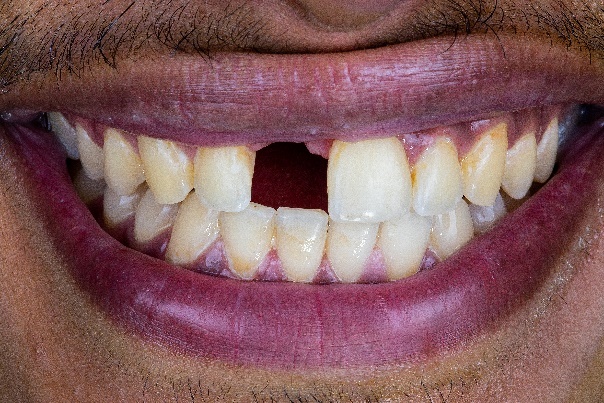

The patient, a 35-year-old male, sought treatment six months after losing his anterior tooth (21) due to trauma. Clinical examination revealed soft tissue depression in the edentulous area, while CBCT imaging showed insufficient horizontal bone width (<4mm) in the region, with normal vertical bone height, adjacent teeth, and occlusal relationships, the patient has high aesthetic demands. (Fig2,3,4,5)